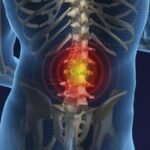

Podemos dividir a coluna em três partes: região cervical, torácica e lombar. A lombalgia é caracterizada por uma dor na região lombar, localizada perto da bacia. A dor pode irradiar para as nádegas, parte posterior das coxas e não muito além do joelho.

A contratura muscular ocorre quando um grupo de fibras se contraem excessivamente, deixando o local rígido. Esse processo contínuo provoca a formação de nódulos no músculo, responsáveis por causarem dor.

Os músculos da região lombar trabalham com frequência em nosso corpo, essencialmente quando abaixamos, levantamos peso e realizamos outras atividades. Além disso, a rotina intensa gera estresse e ansiedade, fatores que também influenciam a contratura muscular.

Quando é constatada que a lombalgia vem de causas musculares, esse distúrbio provoca uma série de erros na contração e no relaxamento das fibras da região.